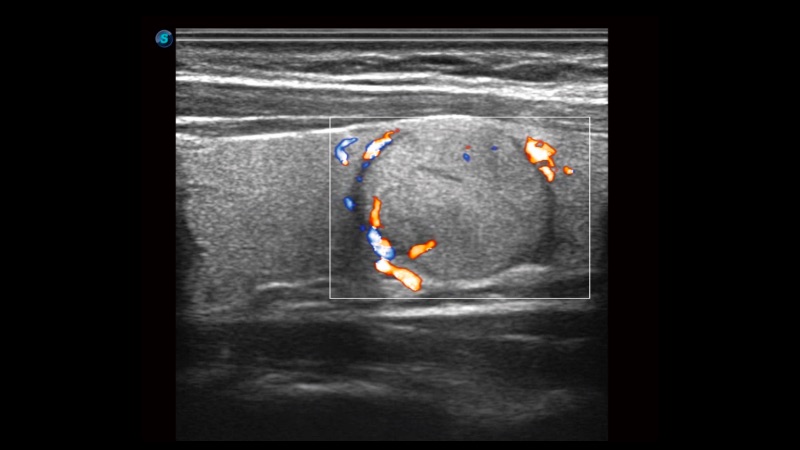

高分辨率血流成像技术提高了对低速血流信号的检测能力。在提高空间分辨率的同时,也克服了血流外溢现象,为用户提供更加真实的血流动力学信息。

通过色彩血流和实时宽景相结合,可观察到完整的静脉或动脉的血流,方便医生检查。实时扫查过程中,如有任何操作失误也可以很容易地进行回扫擦除,而不会中断扫查。